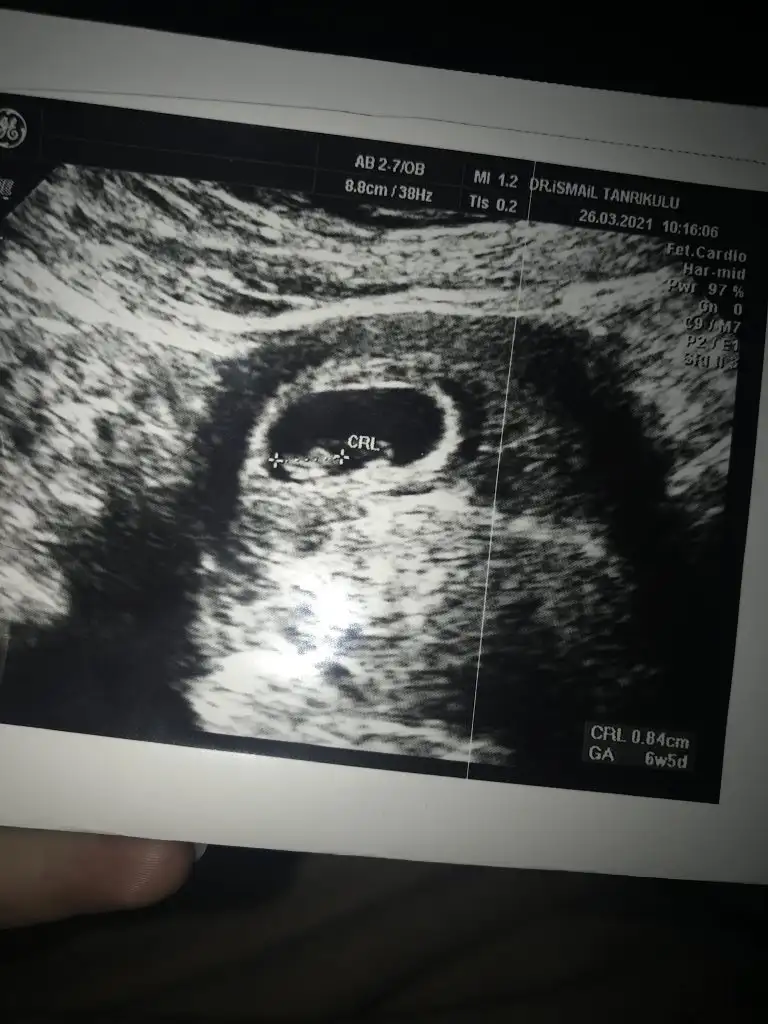

Kiz diyorlar solda oldugu icin ama hic bilmiyorumMerhaba başka sayfaya da yollamıstım ama komse bakmadı6. Hafta vajinal ultrasonum paylasıyorum. Bırısı yorumlarsa sevınırım şuan artık 11. Haftam oldu

6+1 alttan muayene ekran goruntusuMerhaba millet

Benim ultrason karından ama yinede tam anlayamıyorum sağ-sol nasıl olduğunuVajinal ultrasonda bebek kesenin sol tarafında ise kız sağda ise erkek yazıyor internette, karından ultrasonda tam tersi solda ise erkek sağda ise kız yazıyor. Bende daha önce buraya yazdım yorum yapılmayınca araştırdım sizinde bilginiz olsun basit yani kendimizde bakınca anlayabiliriz

Karından ultrasona göre benimki sol da mı duruyor, erkek mi oluyorVajinal ultrasonda bebek kesenin sol tarafında ise kız sağda ise erkek yazıyor internette, karından ultrasonda tam tersi solda ise erkek sağda ise kız yazıyor. Bende daha önce buraya yazdım yorum yapılmayınca araştırdım sizinde bilginiz olsun basit yani kendimizde bakınca anlayabiliriz